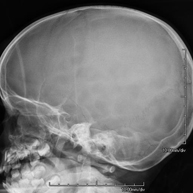

- Skull X-ray

This technique uses X-ray rendered imaging for examining the skull. Indicated for: trauma, premature cranial suture closure.